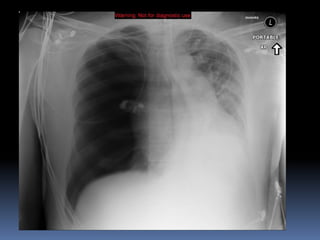

Abnormal Findings Un equalityof chest movement Dullness on percussion Decrease air entry Tachypenic heamothorax chest tube